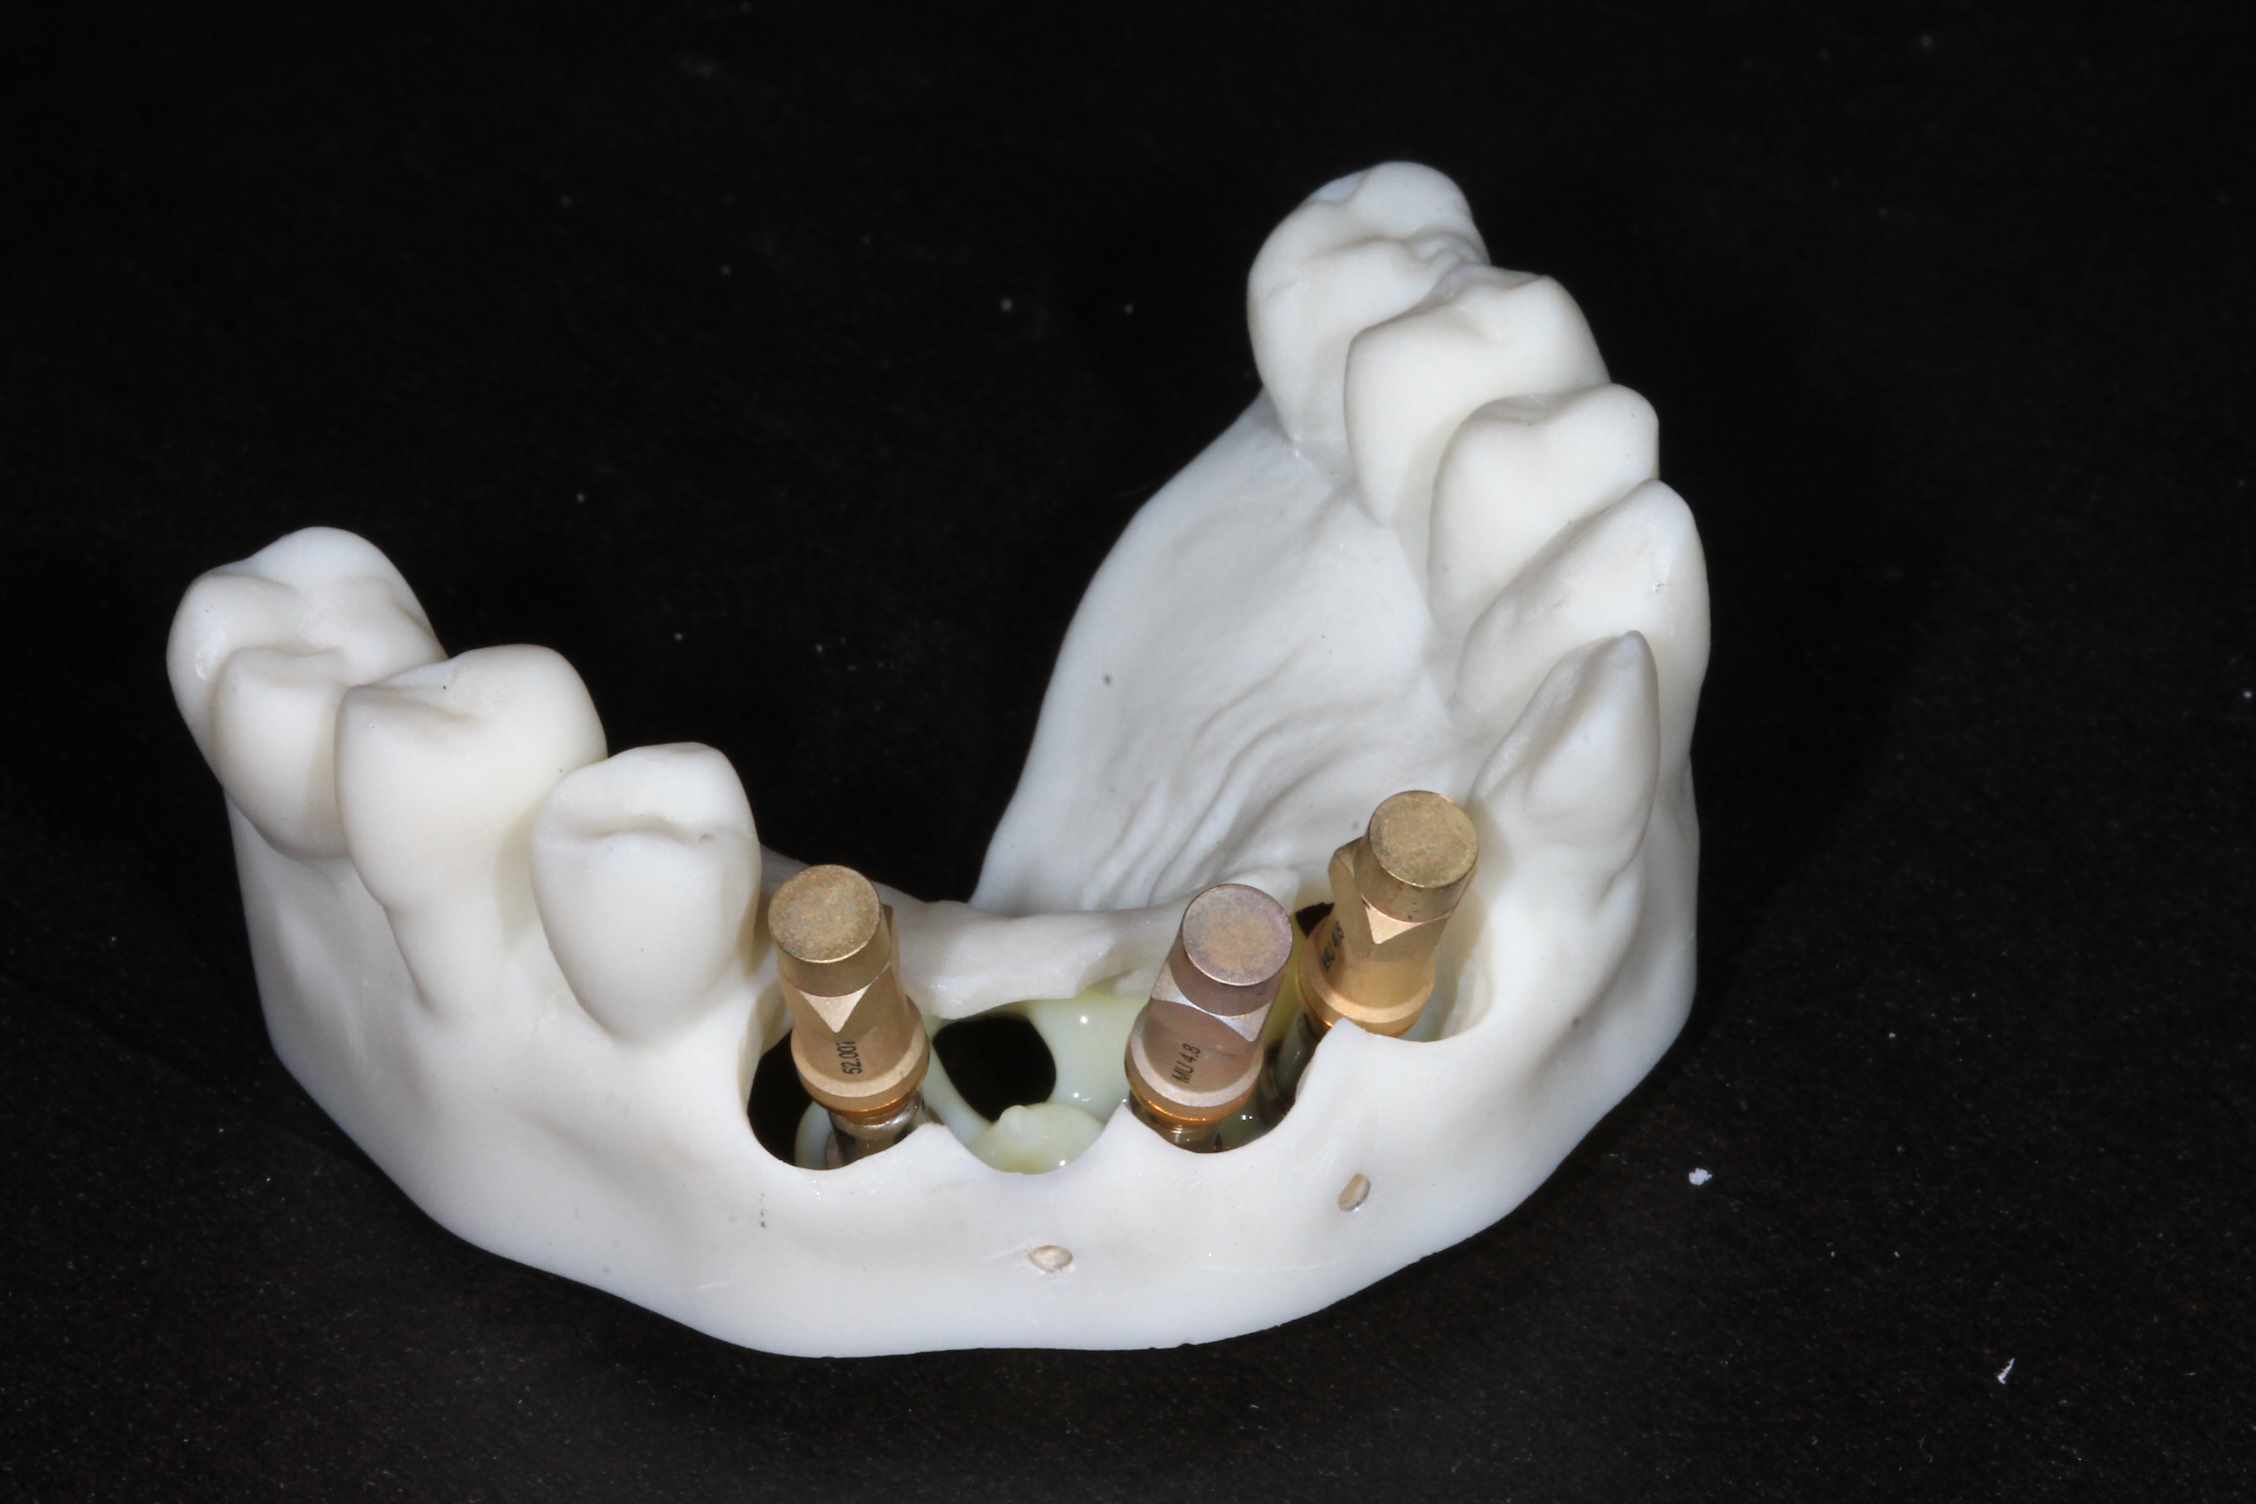

les 4 incisives sup sont à bout de souffle . Planification et export du guide résine avec blueskyplan. Export du modèle osseux et simulation de la chirurgie, comme d'hab selon mon protocole.

Quand les implants sont peu nombreux et proches, un guide résine est suffisant. C'est alors beaucoup plus rapide.

simulation de la chir. scan, matching des elements avec medit design, finition du bridge dana meshmixer.

Pa33xdk33krl7ww8uvpq86f6ffjt - Eugenol

Zob2gos4ti8lvymsvopbr8jvw1ml - Eugenol

Snq1sjrf1y6ymyc4v3vjp1rdo4m7 - Eugenol

J79w231wa4hdmtqrwbwdjptvglu6 - Eugenol